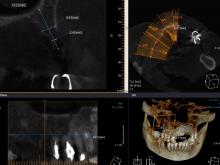

インプラントは、右上57相当部に2本埋入しました。CTで見ても分かるように、骨がとんがっていて通常のドリリングではインプラントをさらに深いところまで入れないといけません。

ということは、インプラントを短くするか、サイナスリフトしないと長いインプラントが入らなくなります。。。

そこで、今回は、オッセオプッシャーを用いて骨の切削量を最低限にしてインプラント埋入しました。